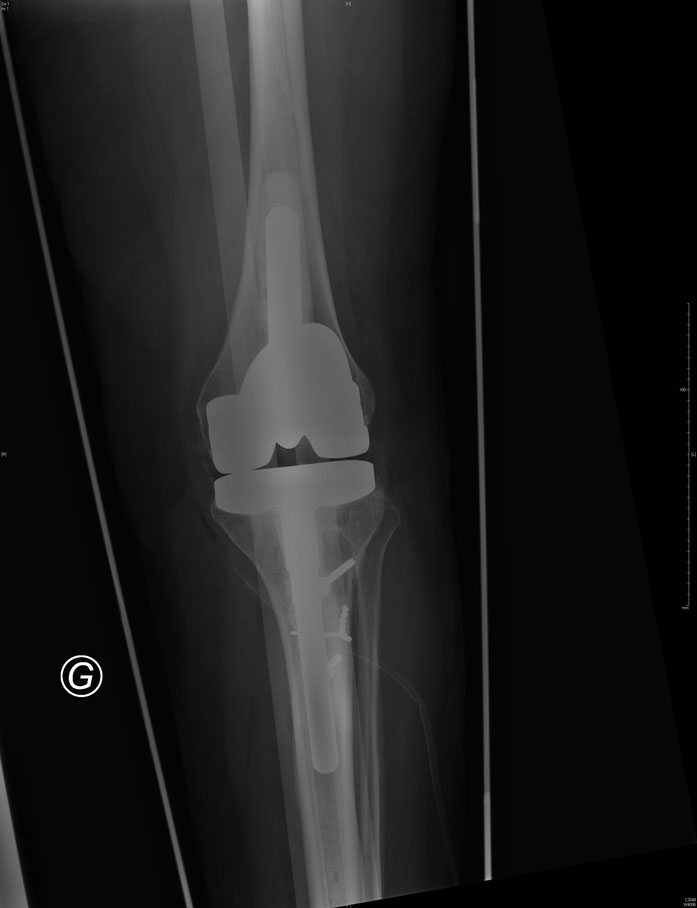

Reprise de prothèse totale du genou

La prothèse totale du genou est une entité complexe constituée de quatre éléments qui s'articulent ensemble lors des mouvements de flexion et d'extension de votre genou. Ces éléments sont :

L’implant fémoral

L’implant tibial

Le polyéthylène intermédiaire

L’implant rotulien

La planification préopératoire est une étape fondamentale au bon déroulement de votre intervention. Elle consiste à localiser précisément les zones de perte de substance osseuse, de dépister une laxité ligamentaire et de choisir les bons implants de reprise.

positionnement d'une nouvelle prothèse de reconstruction contrainte.